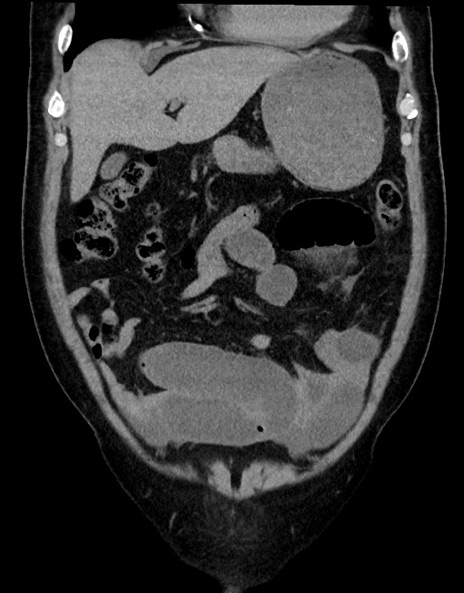

症例15(冠状断像)

【症例】70歳代男性

【主訴】腹痛

【現病歴】今朝から腹痛あり。全体的に痛い。特に左上の方。排ガスが今日はない。冷や汗が出る。

【既往歴】直腸癌術後

【身体所見】左側腹部〜上腹部に圧痛あり。腹膜刺激症状明らかなではない。軽度反跳痛。左下腹部に術後瘢痕あり。

【データ】WBC 7700、CRP 0.02